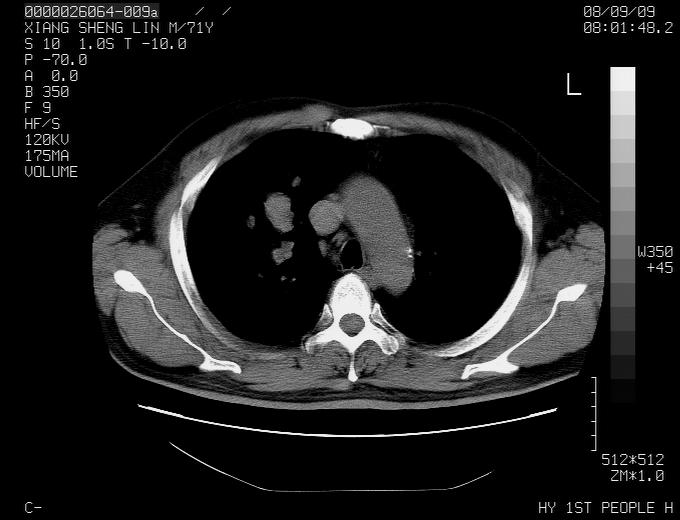

标题: CT15869:男性,71岁,因咳嗽而就诊,请讨论右上肺病变性质 [打印本页]

患者,男性,71岁,因咳嗽而就诊,

典型的右肺中心性肺癌并纵隔淋巴结转移

考虑右肺中心性肺癌并右肺门及纵隔淋巴结转移。

1,右肺中心型ca,气管隆突旁淋巴结转移。